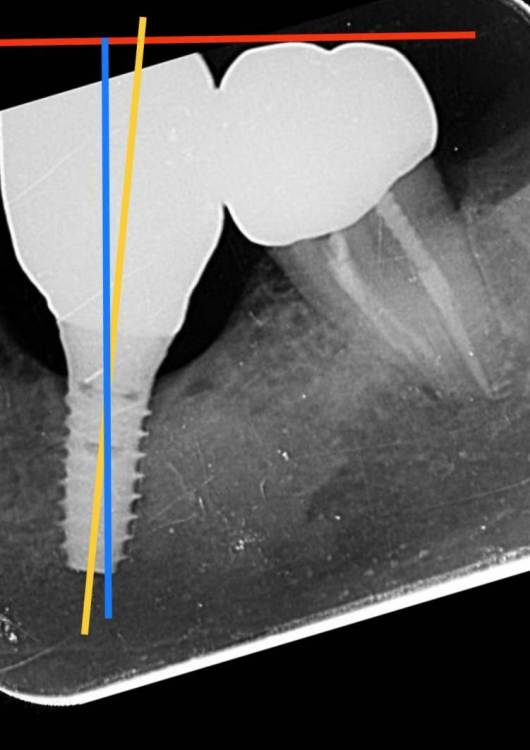

annda Опубликовано 9 ноября, 2022 Поделиться Опубликовано 9 ноября, 2022 (изменено) Имплантат Simplline,контрольный снимок с абатментом ,торк 35. Как вам контроль,какие мысли по зазору между платформой и абатментом? снимок.bmp Изменено 9 ноября, 2022 пользователем annda Ссылка на комментарий

bakagaidzin Опубликовано 13 ноября, 2022 Поделиться Опубликовано 13 ноября, 2022 по мне так недосад небольшой Ссылка на комментарий

bakagaidzin Опубликовано 2 декабря, 2022 Поделиться Опубликовано 2 декабря, 2022 хирургу конечно за такую установку руки оторвать) 2 Ссылка на комментарий

red_butler Опубликовано 2 декабря, 2022 Поделиться Опубликовано 2 декабря, 2022 43 минуты назад, bakagaidzin сказал: хирургу конечно за такую установку руки оторвать) предположу, что хирург обходил остеосклероз 1 Ссылка на комментарий

bakagaidzin Опубликовано 2 декабря, 2022 Поделиться Опубликовано 2 декабря, 2022 @red_butler предположу что он просто криворукий и не понимает как должен быть спозиционирован имплантат) Ссылка на комментарий

Irouil Опубликовано 2 декабря, 2022 Поделиться Опубликовано 2 декабря, 2022 Ну, ангуляция есть, вполне очевидно, но криворукий или нет судить по одному куцому рентгену невозможно, это инсинуация 1 Ссылка на комментарий

АнтонТЛТ Опубликовано 2 декабря, 2022 Поделиться Опубликовано 2 декабря, 2022 На 5° завален относительно окклюзионной плоскости, это много? Ссылка на комментарий

bakagaidzin Опубликовано 3 декабря, 2022 Поделиться Опубликовано 3 декабря, 2022 Вы все прикалываетесь чтоли?) на оси соседних зубов посмотрите Ссылка на комментарий

annda Опубликовано 3 декабря, 2022 Автор Поделиться Опубликовано 3 декабря, 2022 (изменено) Тут как с осью,все устраивает? У тети все зубы врассыпную,5ка ротирована по оси.Непрофессионально,доктор,руки отрывать,по прицельным снимкам:) Но и ,кстати,да,этот камушек просверлить не смогла,заходила два раза.Прошла по касательной. Изменено 3 декабря, 2022 пользователем annda 1 2 1 Ссылка на комментарий